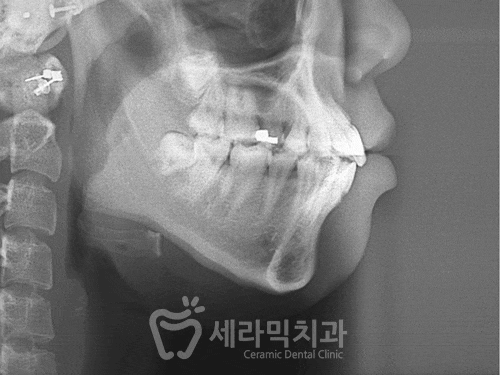

X-ray 사진을 통해서 그 변화를 확인해보겠습니다.

![학동역 치아교정, 수술없이 예뻐져도 되나요? [돌출입교정 전후 달라진 외모] 관련 이미지 8](https://pub-9f2bb3498faf4d1d8714b41df24753e3.r2.dev/content/clinics/archive/z16imuoeq4/naver_blog/seohyun_0425/assets/by_hash/17409d697be02b59ba312d1575e319da76e1693586b64cbc2001981567bb8f3d.gif)

돌출입교정전후 턱끝이 갸름해지는 효과

90도 정도에 뭉툭하던 턱끝이

학동역치아교정 후, 85도 정도로

갸름해졌을 뿐 아니라,턱끝이 아래로 확실히

내려간 것을 확인할 수 있습니다.